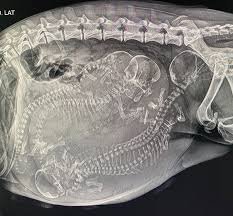

Should always count skulls, because spines can cross making it hard to estimate the right number.